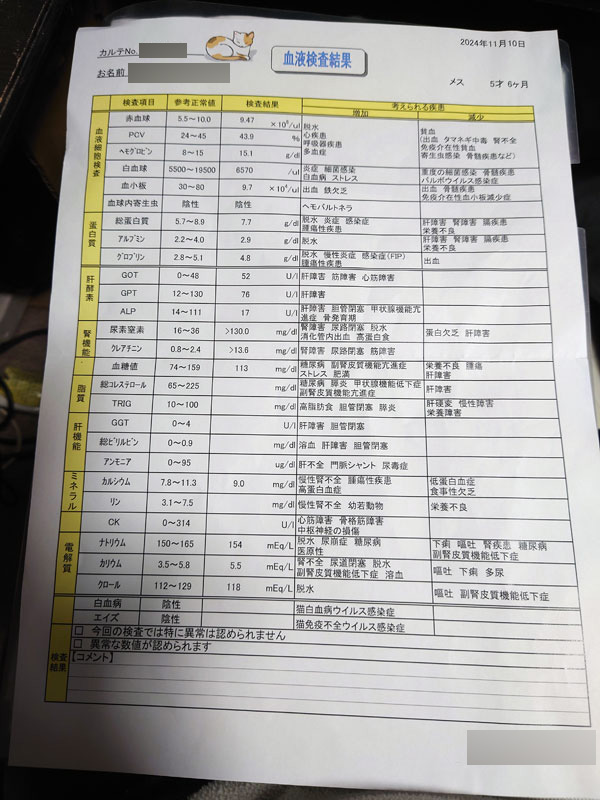

まあコピー本でも書いたんだけど、日記で時系列で見ていこうか。 ほんとコミケ参加もできるかどうかという年末だったのだよ。 9月30日(月) 前川の定期健診でした。 そういえばこの時は、なんともなかったんですよね…  4日(金) LINEギフトで貰っていた誕生日プレゼントが届きました。 ハルト氏より。  じょにぃ氏より。   10月5日(土)  10月6日(日)  7日(月) 自宅警備に精を出す前川。  8日(火) ホットカーペットの上で野生を忘れる前川。  10日(木) 会社で営業O氏のおかげで、エンジニアのK氏とミーティングができました。上司Hと一緒に夜飲み会もしてきました。 オフィスから少し歩きましたが、O氏の希望により餃子のお店に。 帰りに上司Hから11月からの体制を聞かされて大変だなーと思いました。  10月12日(土)  13日(日)  14日(月)  エアコンの下でセンシティブを背負う前川。  17日(木) EK氏の誕生日前夜だったので出前で良い寿司食べました。  19日(土) EK氏の誕生日に、乾燥機を置くための台を買ったのですが、それを組み立てていました。 なかなかパーツが大きい&重くて苦労しました。 乾燥機本体は高いので家計で買うのです。  前川のありがたいポーズ。   25日(金) 仕事で初めて幕張メッセに行ってきました。 自宅からの乗り継ぎがアクセス良くてびびった。  この日はけっこう大変で、 夕方までほとんど立ちっ放しのイベントのお手伝いをしてから、同僚のK氏と一緒に新宿まで移動。☆まっちメインの研修会を実施して、そこから☆まっち幹事の懇親会でした。 金曜日ということもあり、めちゃめちゃ疲れました。 26日(土) 二次裏オフ会で川崎まで行ってきました。 川崎駅の上にあるビアガーデンでした。 翌日のオンリーイベントに参加するettol氏を囲む会だったのが発端だったかと思いますが、朝が大変なので☆まっちはイベントの方は行きませんでした。 アフターは身内大戦へ。  悲しいことに、10年以上酷使してきたiPodnanoをこの日落としてしまって。 どうしても見つからず、サヨナラすることになってしまいました。 楽曲データはPCに入っているものの、あれに慣れていたのでなかなか凹みました。 27日(日)  28日(月) 紅時雨氏が地元の福岡に転居してしまうということが発端で、送別会になりました。飯だぞ氏主催で、月曜日でしたが有休戦法で参加してきました。 7~8人くらい参加してたのですが、北斗氏という大戦プレイヤーの中で有名な検証勢の方も参加していて、ロマサガ2の話をけっこうしました。 北斗氏は人生あがってる組ではなく、普通に働いている裕福層寄りのサラリーマンでした。 ただ、やっぱり繋がってるランカーの話を聞くと、働く必要がない人も多いみたいですね。  11月3日(日)  4日(月) 飯だぞ氏とゲーセンで英傑大戦の配信してきました。 モチベ低いみたいで、ほとんど☆まっちメインでしたが。 しかしアフターがこの日の目当て。 行徳というところまで行って、肉と米ハジメというお店に行ってきました。  この食べ放題に挑戦してみたかったのです。  最初に出てくるのが、ハンバーグ100g、ステーキ150g。 ライス、ドリンクも食べ飲み放題ですが、頼まなければ肉だけでもいけます。  3500円+税でまさかって思うじゃないですか? ところが肉がめっちゃ柔らかくて、たぶん香草か何かに漬けてあって、ソースなしでもうっすら味があります。オニオンソースか塩でいただきましたが、酸味のあるオニオンソースで無限に食べられるのです。 ☆まっちの戦績は以下の通り。 少量ずつおかわりを繰り返しました。 ステーキ150、ハンバーグ200 ステーキ100、チーズハンバーグ100 ステーキ100 、ポークステーキ100 ステーキ200 米1.5 杯 飯だぞ氏が700gくらい頼んだ時の画像がこちら。 飯だぞ氏も当日に向けてコンディションを整えていたそうで、☆まっちより食べてましたね。また行きたい店です。  7日(木) ホットカーペットで暖をとる前川。  組み込み系エンジニアのI氏と営業のO氏を採用メンバーで囲う会でした。 忙しい時期だったので全員揃うまで時間かかりました。  9日(土)  10日(日) 前川の様子がおかしいので病院へ。 ここ2日ほど、ご飯をほとんど食べていないため、連れてきました。 土曜日は朝に少し食べたので、気にしすぎかとも思ったのですが……  血液検査にエコーもやってもらって、腎不全再発です。 このままだと○ぬと宣告されてしまいました。 ちょうど2年ぶりの悪夢です。  サブシステムの手術を勧められましたが、デメリットもあります。 ・50万円くらいかかる ・手術失敗のリスクがある ・成功した後も体調改善しない可能性がある ・成功しても定期的にインプラントの洗浄で通院が必要 最悪、手術から覚めない可能性もあって。 なかなかその場で判断するのは難しかったです。 手術をしても変な後遺症を持ったままつらい猫生が続くだけだったら可哀想ですし、悩みどころでした。 11日(月) 朝一で動物病院へ。 10日の夜に電話で手術を願い出たところ、午前中に手術してくれることになりました。 平日ですがフレックス出社にさせてもらったはずです。  結果は昼過ぎに電話で教えてもらえて、無事終わったとのことでした。 ひとまずホッとしました。 12日(火) 在宅勤務だったので、昼休憩を利用してお見舞いに行きました。 最初扉を開けたときに「シャーッ」って威嚇されました。 家では絶対に見せない、本気モードの威嚇でした。 撫でたら分かってくれたみたいですけど。  13日(水) 退院。 結局もろもろで60万円くらいかかりました。 (しかもこれから維持するのに通院が増える…)  まだ抜糸前なのでエリザベスカラーを付けっぱなしにしなければならず、だいぶ生活しづらそうでした。狭いところは通れなくなりますしね。 お腹の毛と、恐らく点滴用のため腕にも一箇所、毛が刈られていました。 あと恐らく院内でけっこうお漏らししてて、尿っぽい臭いがありました。  あと、やっぱり体内に人口管があるのが違和感あるのか、頻繁にトイレに入ってはおしっこ出ないを繰り返していました。 尿意は感じるが出ない、おかしい、みたいなのを繰り返していて、ちょっと可哀想でした。 今は順応したみたいで、そういうことも無くなりましたが。 17日(日)  18日(月) 経過観察と1回目のサブシステム洗浄のため通院。 血液検査の結果は問題ありませんでした。  23日(土)  それなりに食欲は戻ってきてるので、徐々に体力も戻ってきました。 エリザベスカラーを付けていてもキャットタワーに登ってみせた前川。  24日(日)  抜糸してきました。 やっとエリザベスカラーが外れた前川。   28日(木) 朝の暖をとりにくる前川。  上司Hと隣の課のH氏、3人で新橋の焼肉屋に行ってきました。 確か研修会とかで飲み会を企画したけど、忘年会の予定も並行してたせいで集まりが悪かったけど、H氏のオススメの店に少数精鋭で行くことになった流れだったと思います。 5500円のコースだったんですが、店員さんが全部焼いてくれるタイプの焼肉屋で、めっちゃ美味しかったです。 飲み放題つきでこれは値段もかなりリーズナブルだと感じます。  30日(土)  12月1日(日)  4日(水) 英傑大戦の配信をされてる方のプレゼントキャンペーンに当たったので、景品の絆カード×3が届きました。  5日(木) 採用グループで目標達成のランチ会やってきました。 新宿周辺で予約できるランチのお店というのが少なくて、けっこうお店探し大変だったらしいです。  6日(金) ☆まっちのオフィスビルで、ビンゴゲーム大会をやってきたので参加してきました。特にこれといって欲しいものは当たらなかったので、残業していた上司Hにあげました。 (ノートPCケースとか、水筒とか) で、たまたま残業していた人事のW氏と一緒に飲みに行こうという話になったので、オフィス1Fの居酒屋で軽く飲んで帰りました。 W氏が酔っ払うと、しっかりしたことを言う割りに記憶なくすのおもろい。  7日(土)  お腹の毛はまだ戻らないけど、抜糸後の傷はかなり分かりにくくなってきた前川。  8日(日) サブシステム2回目の洗浄のため通院。 次からは3ヶ月に1回の頻度になります。  11日(水)  14日(土) すえっち氏、こずへ氏と忘年会してきました。  こずへ氏からキャンピングセットを貰いました。 誕生日プレゼントのお返しだそうです。 まあソロキャンはしないと思いますが、せっかくなので家で使わせてもらいます。  すえっち氏の息子さんがきっかけで、ベイブレードが流行っていると聞きました。あとは近況報告とか。 頓挫してしまった石川の旅行もありますが、前川の体調のこともあるので☆まっちから長期旅行は提案しづらく。 15日(日) 連日また新宿に来て、スポーツランドで英傑大戦の配信をしてきました。 途中からキャンベル氏、真沙氏も到着して、交代でプレイしました。 小喬ペロペロのオフ会が今年は無理かと思われたのですが、この日はそのままきゃろ氏と合流してオフ会やってきました。  キャンベル氏が結婚したという報告があったばかりなので、お祝いのケーキを頼んでおきました。 全体的にサービスの良いお店でした。  真沙氏が転職先まだ確定してていないらしく、退職することは決めたものの次をどうするか、というところで困っているようでした。 今の会社でもそれなりに責任のある立場のようですし、家族も子供もいて年収を下げる転職をするわけにもいかないでしょう。 16日(月) なんだそのポーズは  17日(火) 笛てんてーにフォローしてもらえた記念。  19日(木) 会社で、グループ人事部という本社側の人事組織と混成の忘年会でした。 入社したばかりの☆まっちはほとんどアウェイなのですが、(タダだと聞いたので)敢えて参加してみました。 シュラスコのお店で、待ってるとどんどん肉持って来てくれるので、断らない限りどんどん皿が肉まみれになっていくお店でした。良かった。  開場が溝の口だったのですが、駅近だったのでGIGO溝の口にも寄ってみました。   20日(金) で、翌日は自分とこの採用グループだけの忘年会でした。  少し前にやった社内のプレゼン大会の結果発表があったのですが、☆まっちは2位でした。 1ポイント差でN氏が一位だったということでしたが、まあちょうど結婚したばかりなのでN氏が優勝でちょうど良かったかもしれません。  21日(土)  23日(月) どうした人間。  24日(火) パジャマユウカが可愛すぎてプレゼント全部投入してしまいました。  26日(木) 仕事納めでした。 帰り隣の課のS氏と一緒になったので、ラーメン食べてきました。 新宿シンちゃんラーメンという店を教えてもらいました。 ちょっと裏路地に入ったところなので、自力では気付かなかったと思います。感謝。 Fラン就職チャンネルの話とか、所得の話とか色々話しました。 前職の話も少し聞かせてもらいました。  28日(土)  年末を締めくくる前川の横顔。  29日(日) コミックマーケット105 1日目。 実はアーリー全落ちしてて、一般参加のリストバンドも気がついたら完売してたので昼から行くつもりだったんですが、ジャック氏が前日にチケット譲ってくれる話をくれたので、朝早くから集合場所に向かいました。   お目当ては少なかったので、いくつかジャック氏の頼まれものを購入したあと、最近相互になった東7で刹那氏にご挨拶。 あと、西館でハルト氏がご友人のブースでアドマイヤベガのコスプレをしているということだったので、そっちへも移動してご挨拶と撮影。 久しぶりだったので近況の話も立ち話しました。  それから企業ブースもぶらっと周り、1人で晩ご飯食べて帰りました。 30日(月) C105 2日目。 2日目はProject-P☆として受かっているので、すえっち氏と待ち合わせて一緒にサークル入場しました。  ☆まっちは買い物を早々に終えて、ブースで売り子をしていました。 だいぶすえっち氏に買い物を頼んでしまいました。 架聖氏がブースにご挨拶に来てくれました。 こちらから後で挨拶に行くリストに入っていたのですが。 クッキー美味しかった。  すえっち氏は夜に仕事があったので、少し早めに撤収しました。 品川でバニー氏、一二三氏と合流して打ち上げてきました。 バニー氏が仕事を辞めててびっくりしました。直近のこと過ぎて、あまり未来の話はできませんでしたが。  31日(火)  コミケ最終日が大晦日ではなかったので、戦利品を飾ったり買い物に行ったりする余裕がありました。      今年の年越しそばは普通の天ぷらそば。  これは年末カウントダウンのテレビを見ていたら寄ってきた猫。  2025年1月1日(水)  2日(木)  この日はちょろっと新宿のメロンブックスに行ってきました。 4日(土) 日帰りで名古屋に行ってきました。 目的は地元のFEオフ会が久しぶりに開催されたので、それ目的です。 ただ、開催が14:00からレンタルスペースになってしまったので、昼食一緒できる人に片っ端から声をかけた結果、かなり久しぶりに後輩Sが名古屋まで出てきてくれることになりました。 後輩Sは1社目で☆まっちが社内講師をしていた頃の新入社員ですが、今もまだ1社目に在籍していて、もう15~16年くらい勤続しているそうでした。  一人暮らしをした時も家が近所だったので引越し手伝ってくれたんですよね。後輩Sが当時の写真を持っていたのウケたので撮らせてもらいました。  子供1人いて、以前と同じエリアに建売の一軒家を購入していました。 幸せそうで何より。 それから名古屋駅の西側へ移動してFEオフ会へ。 参加者はA-K氏、ごろ~氏、コニャン氏、ジャック氏、空羅氏、初恵氏。 と、各自の子世代が数名。 エルフィン氏が体調不良で欠席だったんですよね。残念。  ごろ~氏がロマサガ2大好き勢で、難易度ロマンシングでやりこんでいたので神リメイクだよねーという話をしました。 一方コニャン氏は家が厳しいらしくゲームを買って貰えないとのこと。ドラクエ3リメイクをやりたがっていましたが、妻帯者って大変だなあと思いました。 プロジェクターがあったので、ジャック氏のソフトでぷよぷよテトリスをやりました。  皆さん家庭もあって二次会も開催されなかったので、ジャック氏と名古屋のメロンブックスに寄って解散。☆まっちはそれからコムテックタワーで少し遊んでから、矢場とん食べて帰りました。  5日(日)  6日(月) 年始の初出社日。 いろいろやることがあって忙しいのですが、とりあえず1/1入社の方の入社対応があるので、そこで大忙しでした。 しかし、この前日くらいからお腹が痛かったんですよね。 そして夜早く寝ても治らないという。 7日(火) 求人原稿の取材があったので、この日もオフィス出社してカメラマンとライター、被写体の方々との間で行ったり来たりして大変でした。 が、お腹の痛みが絶好調で、まともに歩くのもつらい状況だったので、上司からもメンバーからも帰った方がいいと言われて帰宅しました。 家で在宅勤務する発想もあったのですが、収まらないのでその日のうちに病院へ駆け込みました。 まずインフルかコロナどちらかの検査があり、そこは陰性だったので触診、血液検査、尿検査を経て、CTまで撮って、告げられたのは憩室炎という診断結果でした。 大腸のひだの部分に汚物が溜まって炎症を起こしているらしく、それがかなり重度なので、とりあえず抗生剤の点滴と飲み薬の投与で様子を見ることになりました。 しかし大きい病院に行ったので、待ち時間がかなり長く、すべて点滴が終わった時には19:30とかでした。 待ち時間が苦痛でした。点滴しても全然痛みが引かないし。 そして重大なことを言われたのですが、当面は水以外は飲み食いするなとのことでした。緑茶すらダメ。マジで水だけの食生活が始まったのです。 8日(水) 痛みは引かず、毎日午前休とって午前中は通院して採血と静脈点滴。 午後からは家で在宅勤務なのですが、この日はけっこう手につきませんでした。とにかく病院の待ち時間が苦痛でした。 意外と空腹はつらくなかったです。 ちなみに病院の往復は毎回タクシーで移動しました。EK氏は普通に歩いて通院している病院なのですが、とても歩ける気がしませんでした。 腹痛に加えて発熱、間接の痛み、頭痛もあり、お腹が痛い以外に熱っぽい症状もあるのです。 9日(木) 少し楽になってきましたが、通院を続けます。 血液検査の結果も少しだけ改善しました。 しかし腸に穴が空いたら今よりずっと痛くなるから、夜間でもいいから急患で来るように念押しされました。入院やら手術の一歩手前にいる感覚がありました。 10日(金) だいぶ楽になってきました。 医学の力に感謝しながら通院したところ、いったん様子見するので、あとは投薬だけで様子を見ようということになりました。 1/15(水)までは一応、消化に良いものなら少し食べてもいい、ということを言われ、断食から開放されました。 11日(土) 家でゆっくりしていました。 この一週間、かなり睡眠時間が長かったはずなのですが、まだ眠れる。 ロマサガ2の2周目がだいぶ進みました。 難易度はノーマルで、今回は南方政策にて人魚イベントをジェラールでクリアしました。 これ以降は女性皇帝のみでクリアするゆるい縛りプレイです。 1回目でイーリス加入できなかったので、女性ユニット全員仲間にしたいんですよね。  この頃に食べていたのは、蒸しパン、鯛ほぐしごはん、鮭茶漬け、ささみとほうれん草のしらす和えなど。 14日(火) ☆まっちで暖をとる前川。   15日(水) 通院。 検査はすぐ終わり、問題ないので徐々に食生活を戻してヨシということになりました。入院とか手術にならなくて良かった。 断食生活のおかげで肝脂肪まで改善してしまいました。 17日(金) 人間くさい座り方をする前川。  18日(土)  19日(日)  |